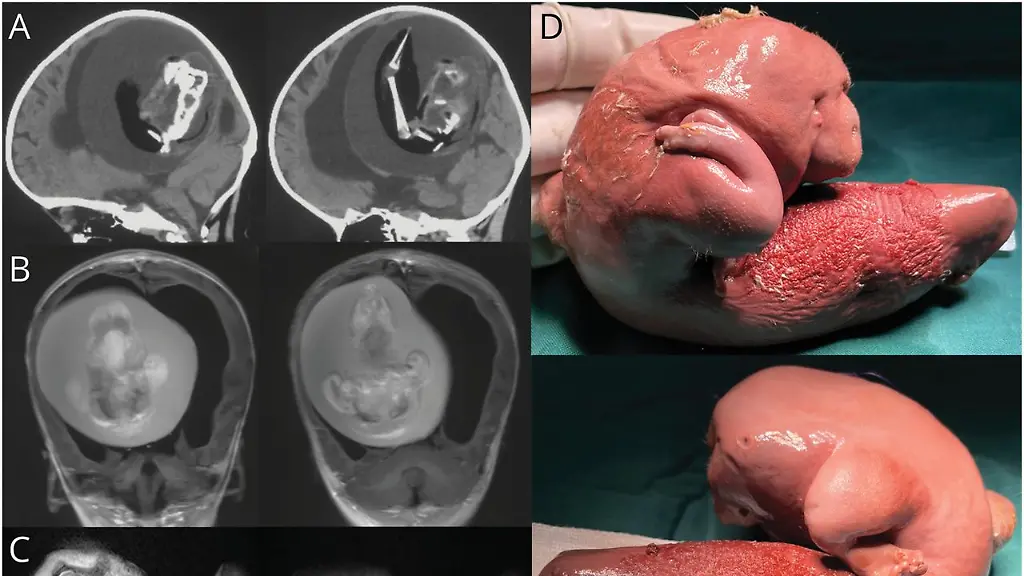

Die Einjährige wurde wegen motorischer Verzögerungen und einem vergrößertem Kopfumfang in ein Krankenhaus gebracht und dort untersucht. Die Ärzte machten mit Computertomografen Aufnahmen von ihrem Kopf und sahen bereits in diesen Aufnahmen einen fötusähnlichen Einschluss, den sie in einer anschließenden Operation entfernten, untersuchten und genetisch analysierten. Sie stellten dabei fest, dass es sich tatsächlich um einen Fötus handelte, der genetisch ein Zwilling des Mädchens war.

Schätzungen zufolge kommt es in einer von 500.000 Geburten zum parasitären Zwilling. Er entsteht, wenn sich ein fehlgebildeter Fötus während der Schwangerschaft in den Körper seines Zwillings bewegt. Dieser Fötus ist selbst nicht überlebensfähig, kann aber immer größer werden und verschiedene Zelltypen ausbilden und so zur Gefahr für Betroffene werden. Weltweit sind bisher weniger als 200 Fälle bekannt.